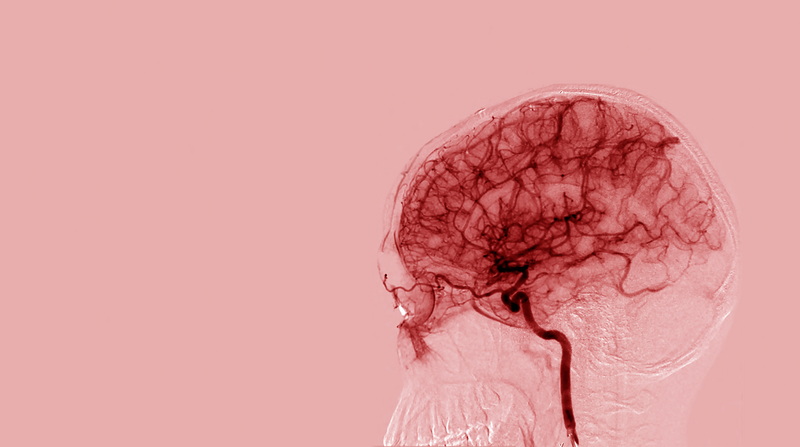

Morning blood pressure values were higher in patients with ICH, with greater median values and wider interquartile ranges for both systolic and diastolic measurements. Comparisons between AIS and ICH patients showed generally higher blood pressure variability measures (e.g., SDSBPV, 24HRCV_SBPV) in the ICH group, although not all differences were statistically significant. The day/night ratio was slightly lower in the ICH group, while both groups exhibiting negative dipping percentages (Supplementary Table 3 and Figure 10).

Figure 10

ICH generally has higher BP variability (SDSBPV, SDDPBV, and 24HRCV) compared to AIS. Day/Night ratio is slightly lower in ICH. SBP Dipping % is negative for both AIS and ICH, with AIS showing a slightly greater dip. SDSBPV, Standard Deviation of Systolic Blood Pressure Variability over 24 h; SDDBPV, Standard Deviation of Diastolic Blood Pressure Variability over 24 h; 24HRCV_SBPV, 24-h Coefficient of Variation of Systolic Blood Pressure; 24HRCV_DBPV, 24-H Coefficient of Variation of Diastolic Blood Pressure; Day/Night Ratio, Ratio of average daytime to nighttime BP (values >1 suggest non-dipping); SBP Dipping %, Percentage decrease in systolic BP at night compared to day (negative = dipping); DBP Dipping %, Percentage decrease in diastolic BP at night compared to day (negative = dipping); Morning BPS, Morning Systolic Blood Pressure (measured between 6–10 AM); Morning DBS, Morning Diastolic Blood Pressure (measured between 6–10 AM), AIS, Acute Ischaemic Stroke; ICH, Intra-Cerebral Hemorrhage.